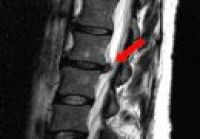

- Bandscheibenerkrankungen

- Einengungen des Wirbelkanals

- sonstige Erkrankungen der Wirbelsäule